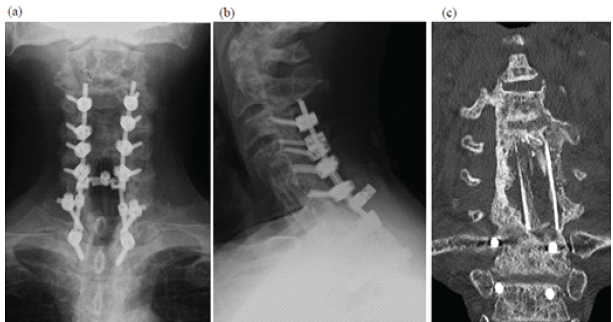

He was diagnosed with delayed esophageal perforation and pyogenic spondylitis with associated myelopathy and was referred to our department. On admission, blood tests showed mild inflammation (white blood cell count 5,900/µL; C-reactive protein 0.31 mg/dL) and hypoalbuminemia (3.5 g/dL). His myelopathy continued to worsen, likely due to instability from vertebral osteolysis. Posterior decompression and fusion (C3–T2 fusion with C3–T1 laminectomy) and gastrostomy were performed first, resulting in mild neurological improvement. Three weeks later, anterior surgery was performed in collaboration with head and neck, esophageal, and plastic surgeons. A right-sided incision – opposite the initial surgical approach – was used. A 20-mm defect in the posterior esophageal wall was identified where it contacted the cervical implant and was filled with infected tissue. After debridement, the left fibula was grafted into the C4–C6 vertebral space. The esophageal defect was sutured with endoscopic confirmation from within the lumen. A right pectoralis major myocutaneous flap was then placed to cover the repair and fill the space between the esophagus and reconstructed vertebra. A tracheostomy was added (Fig. 5).

Figure 5: Post-operative plain radiographs and computed tomography image after staged reconstruction surgery. Frontal (a) and lateral (b) plain radiographs and coronal computed tomography images (c) at 1 year postoperatively are shown. Bony union has been achieved.

Total operative time was 561 min with an estimated blood loss of 710 mL. Postoperatively, the patient received cefepime (3 g/day), metronidazole (1500 mg/day), and micafungin (100 mg/day) for 6 weeks with no recurrence of infection. He underwent rehabilitation for dysphagia and received gastrostomy-based nutrition until oral intake began 4 months after surgery. The tracheostomy and gastrostomy were closed at 5 and 8 months, respectively. His myelopathy gradually improved, allowing him to walk with a cane, and his cervical JOA score increased to 10 at 9 months postoperatively.